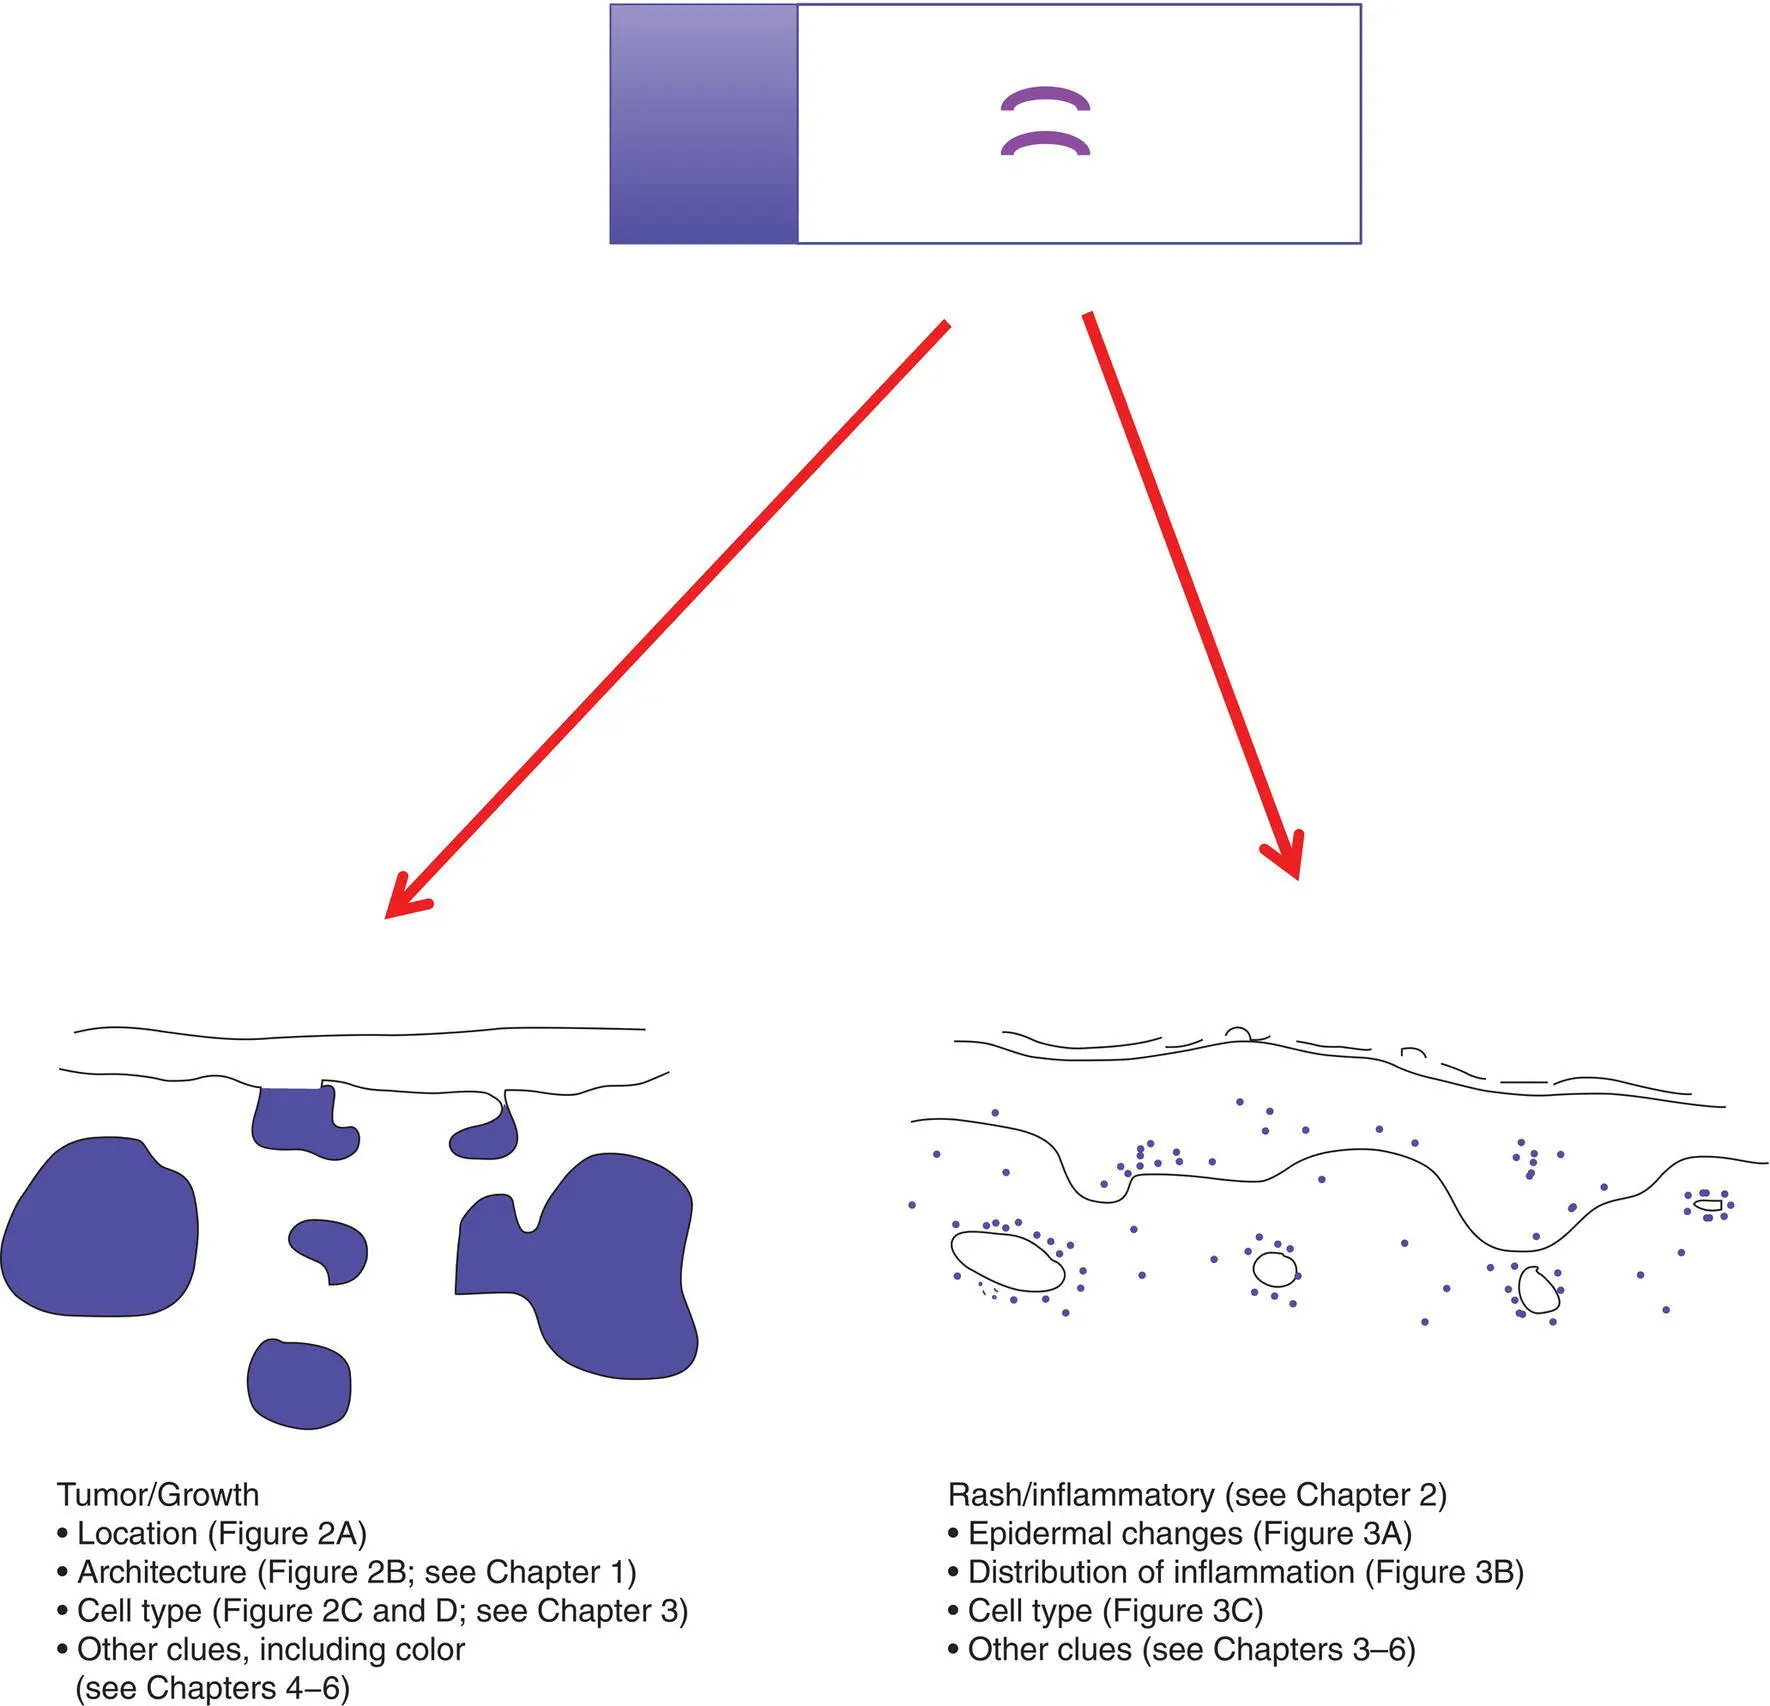

Figure 1 Gestalt impression of a slide

A major initial breakpoint in evaluating a specimen on a slide is the determination of the type of process: tumor/growth versus rash/inflammatory

NoteIn some cases, it is not readily apparent if the process is a tumor or an inflammatory process (examples include mycosis fungoides, a form of cutaneous T‐cell lymphoma, as well as deep fungal infections, which can induce florid epidermal hyperplasia mimicking a squamous cell carcinoma).

Figure 2(A)Location of the tumor

Important characteristics to consider for a tumor/growth include location (A), architecture (B), cell type (C), and benignancy versus malignancy (D). The eye can be trained to focus in on the blue areas (figure–ground separation; grouping)

Dermal tumors can have various architectural patterns

NoteBenign tumors are often symmetric with a pushing border, and malignant tumors may be asymmetric and infiltrative.

“Rash”: key concepts

The eye can be trained to focus in on the blue areas (figure–ground separation; grouping)

Key features include epidermal changes (A), distribution of inflammation (B), and inflammatory cell type (C)